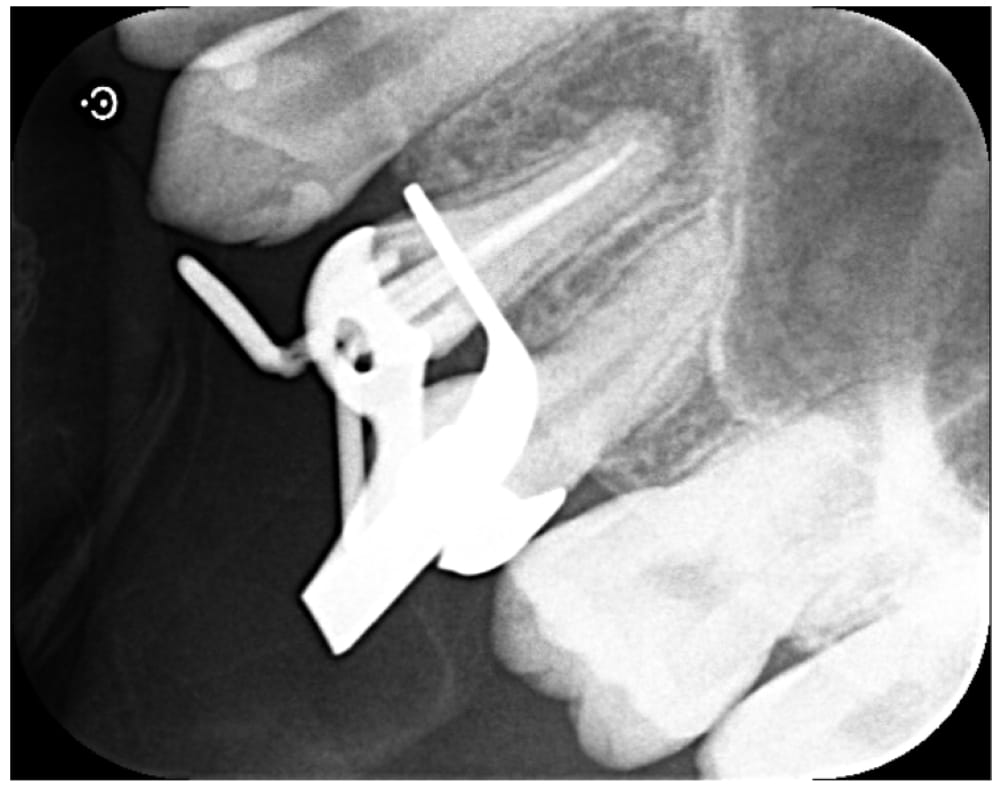

金属製のスクリューポストが入っていたため、残存歯質に負担がかからないように超音波の振動で除去を行いました。比較的シンプルな根管形態であったため、治療は1回で完了し、ファイバーポストを併用してラバーダム防湿下でコア築造まで行いました。

| 根管充填 | バイオセラミックシーラーを用いたHydraulic condensation technique |